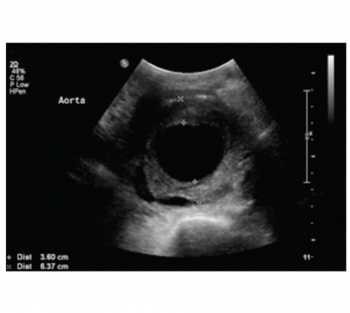

Despite vigorous fluid resuscitation and irrigation, the gross haematuria persisted and his blood pressure remained low. An urgent ultrasound of the abdomen was done the following day. A massive aortic aneurysm measuring 6.5cm in diameter (see Figure 1) was revealed. There was also some fluid collection in the abdomen indicating that there was a possibility that it was a rupturing aortic aneurysm.

Figure 1. Abdominal ultrasound scan showing an aortic aneurysm measuring 6.5cm in diameter(click to enlarge)